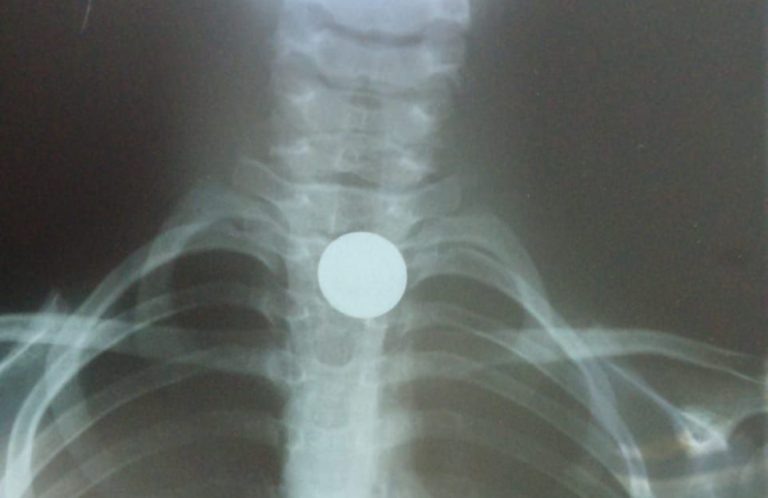

Московские хирурги достали из пищевода четырехлетнего малыша монету

Часто маленькие дети кладут в рот все, что попадает им под руку. Так случилось и с четырехлетним малышом, который проглотил монету. К счастью, инородное тело не попала в дыхательные пути. Оно застряло в пищеводе, сообщает столичный Депздрав. Ребенка доставили в приемное отделение ГКБ имени М.П. Кончаловского, где хирурги обследовали его и в течение нескольких минут достали монету. Как отметил врач-эндоскопист центра Евгений Горькин, даже мелкий, гладкий предмет, прилипнув к стенкам пищевода, в течение нескольких часов может привести к пролежню стенки и дальнейшему некрозу (отмиранию тканей). Более того, есть вероятность перфорации — это сквозное повреждение, при котором нарушается целостность всех слоев стенки пищевода, подчеркнул он. Поэтому врачи призвали родителей при проглатывании ребенком любого предмета незамедлительно обратиться в больницу. Ранее Вести Московского региона сообщали, что родившая 700-граммового ребенка жительница Люберец вернулась в роддом за вторым.

Фото: mz.mosreg.ru Анфиса Слепцова